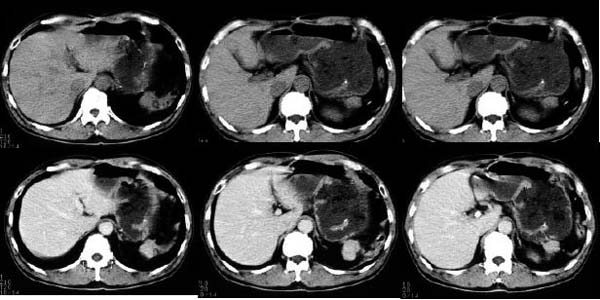

- Age/Sex: 76F

- Chief Complaint: 嫻晹堎忢堿塭

- Images: (click each image to

magnify)

- X-CT

-

- Nuclear

Tl-201 Early

Tl-201 Delayed

F-18 FDG